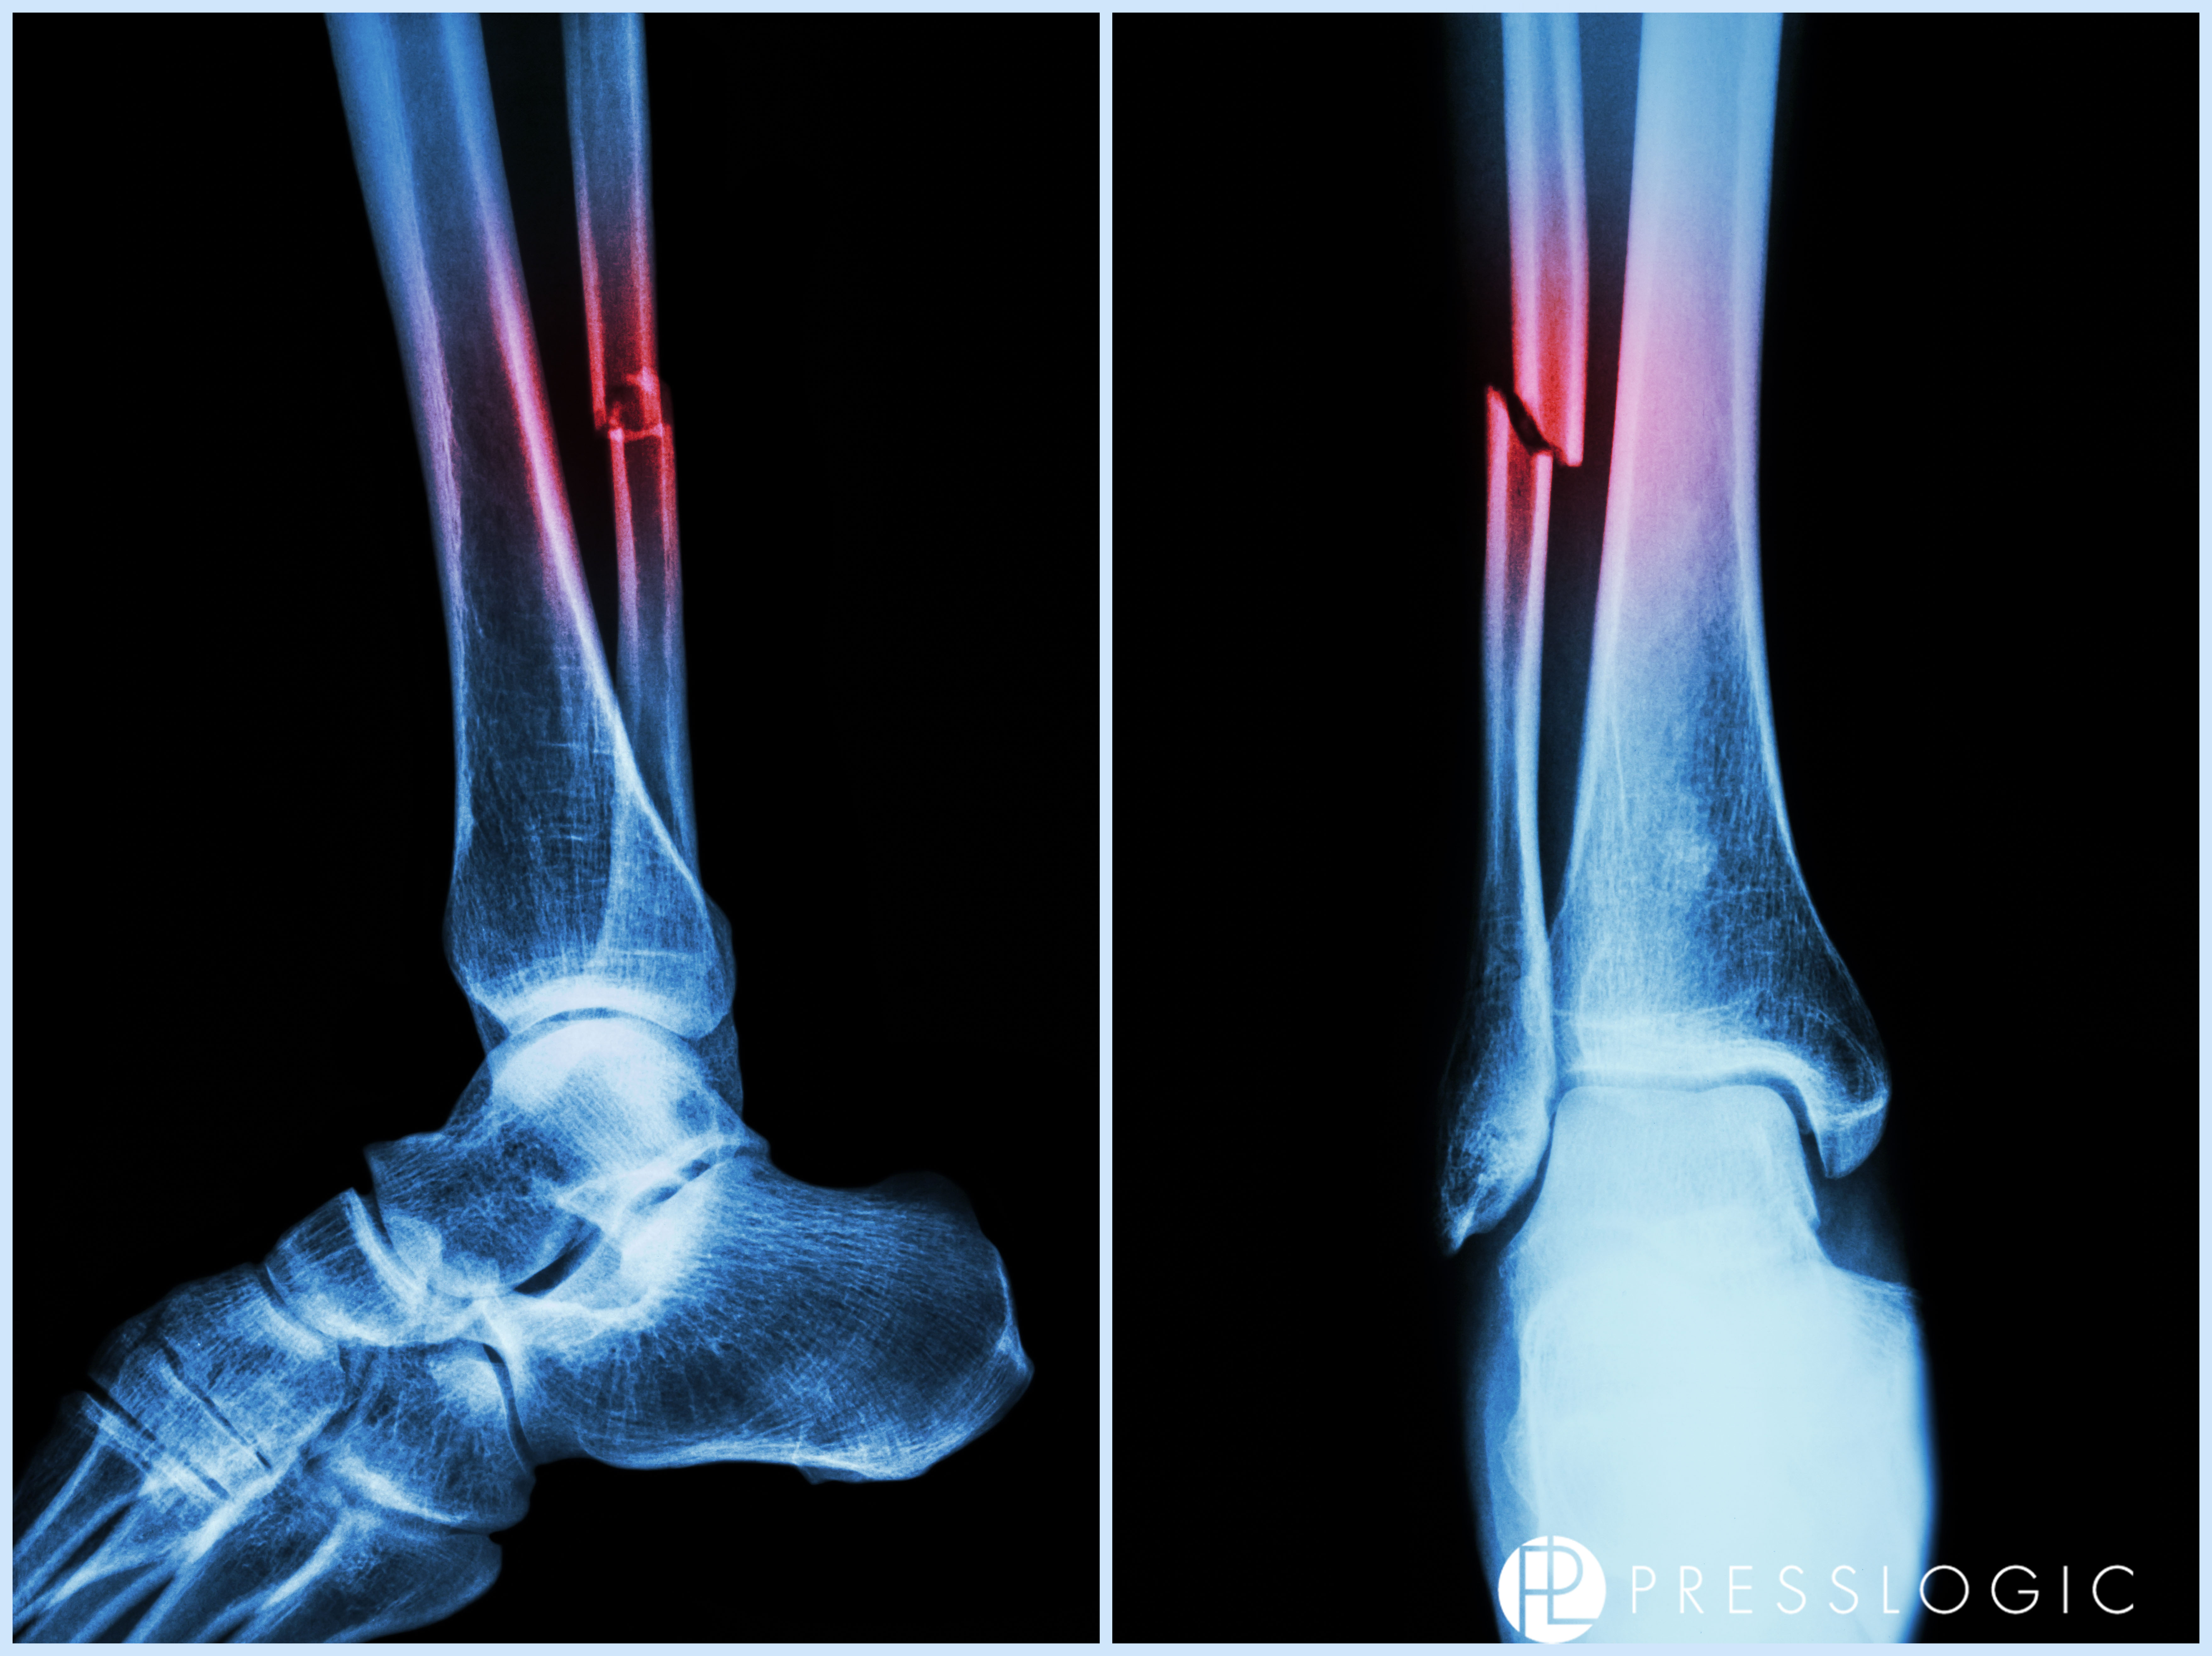

很快消防隊和救護車來了,一堆消防員圍著的士,評估和討論怎樣處理,他們先把Tracy送去醫院。在醫院急症等候時,契女的爸爸Joe到了,她就情緒失控地狂哭,誰也沒辦法。想媽的孩子...... 好無助!!  由於大家的傷勢不一,分開去照X RAY, 見醫生, 洗傷口, 安排住院等。突然聽到Joe通知說Tracy 2條腿都斷骨了,左腳大腿骨斷開3節,右腳腳踝也碎骨了,情況初步不太樂觀!!!   真的忍不住眼淚崩潰了!!!!!!!!! 手腳都變冰冷而且在抖!!  怎麼會斷了呢?怎樣能接受呢?  肚裡的BB怎麼辦呢?  後來才了解傷勢嚴重是因為撞擊那刻Tracy嘗試用腳撐住前座位,希望能撐住頂著女兒,讓她減少踫撞!  結果是保護做到了,可惜就變成她傷得最嚴重。

經過漫長的住院治療,不可下床,不能走動,不少於10個小時的接合手術,腿內上螺絲,多次的X-RAY,很感恩很幸運她慢慢康復。Tracy為了能早日回家照顧女兒,一直超堅強超樂觀地去面對,意志力超強,勤力的忍痛做物理治療。充滿正能量的她,值得讓人敬佩!!

以下圖片已獲得Tracy的同意POST,以此文來紀錄我們曾經經歷過生死後,更懂得珍惜生命!! 媽媽萬歲!!